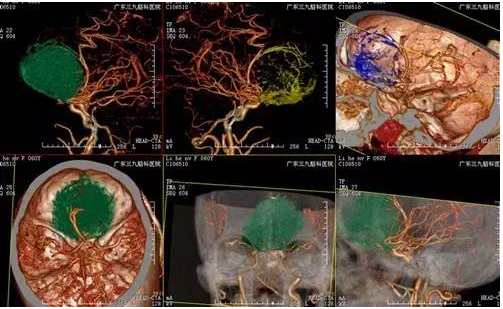

↑术前CTA

李阿姨,62岁,断断续续头痛6年,当地医院治疗能有所缓解,近半年间断出现少语发作,为求进一步治疗来我院就诊,入住神经外一科,MR提示前颅窝底占位性病变,呈均匀强化,基底位于前颅窝底,病变大小约5.9*5.3cm*4.9cm,术前CTA,肿瘤血运丰富,大脑前动脉受挤压后移,考虑嗅沟脑膜瘤。

手术是治疗嗅沟脑膜瘤特别是巨大嗅沟脑膜瘤的唯一有效方法。巨大嗅沟脑膜瘤的切除存在一定难度:(1)术中额部骨瓣需钻孔足够低,暴露颅底;(2)额窦开放需封闭好,防止继发颅内感染;(3)避免反复牵拉脑组织造成术后水肿加重;(4)肿瘤供血丰富,需暴露后处理基底、切断血供(5)后极常累及垂体、视交叉,处理时需减少对垂体柄、大脑前动脉及视交叉的损伤。本例患者肿瘤供血丰富,术前肿周水肿明显,术中出血约200ml,未输血,术后恢复良好,未有明确并发症。